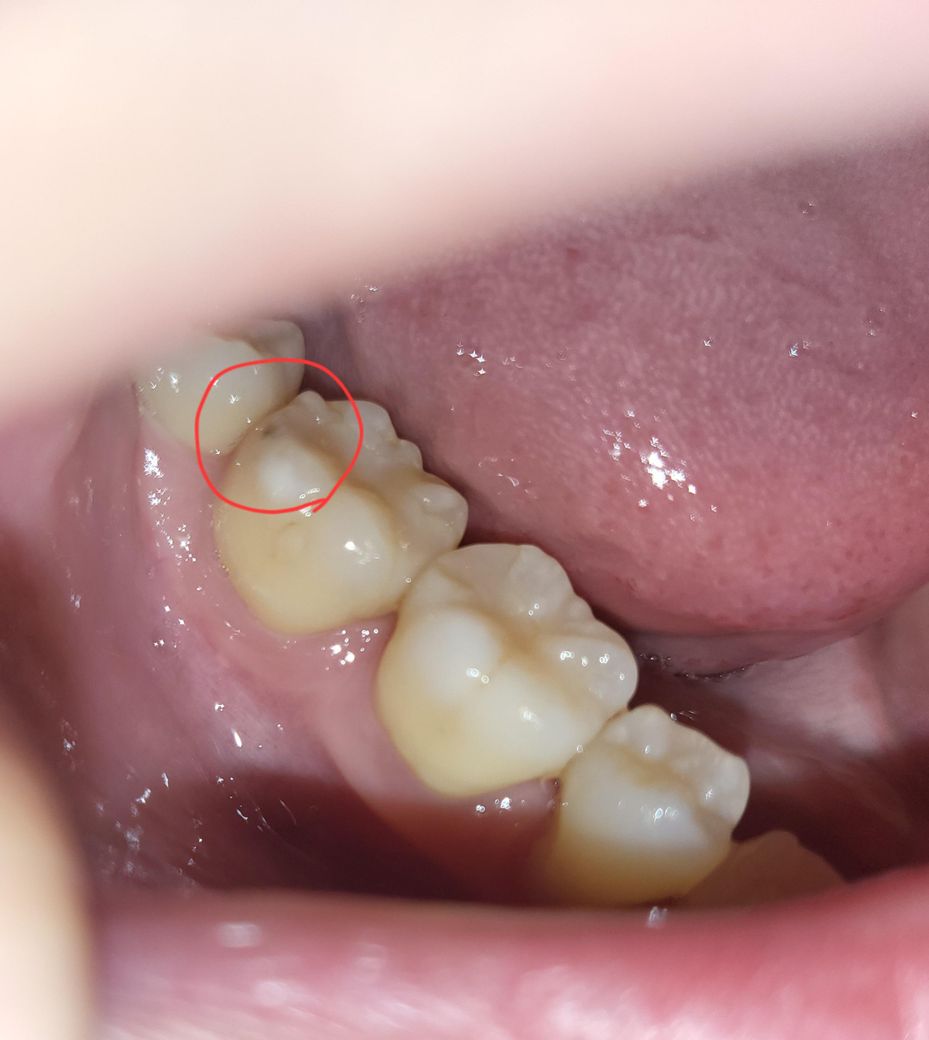

사랑니 앞 어금니 쪽에 검은 점이 박혀 있는데 충치일까요??

양치하다가 발견했는데 마침 오늘 치과도 다녀왔는데 못 발견한 게 이상하네요.. 사랑니 바로 앞 어금니인데 어금니 뒤쪽에 검은 점이 박혀있어요.. 충치일까요?

사진상으론 충치로 보이긴 합니다만 치료가 필요한 정도일지는 치과용 기구로 긁어보고 거친 느낌이 드는지 봐야 합니다 추가적으로 충치 깊이 파악을 위해 엑스레이도 찍어보면 좋을 것 같습니다

사진상으로는 충치가의심이 됩니다. 충치가 정지형인지 진행형인지 확인해보기 위해 치과에 방문하여 진료를 받아보길 권합니다.